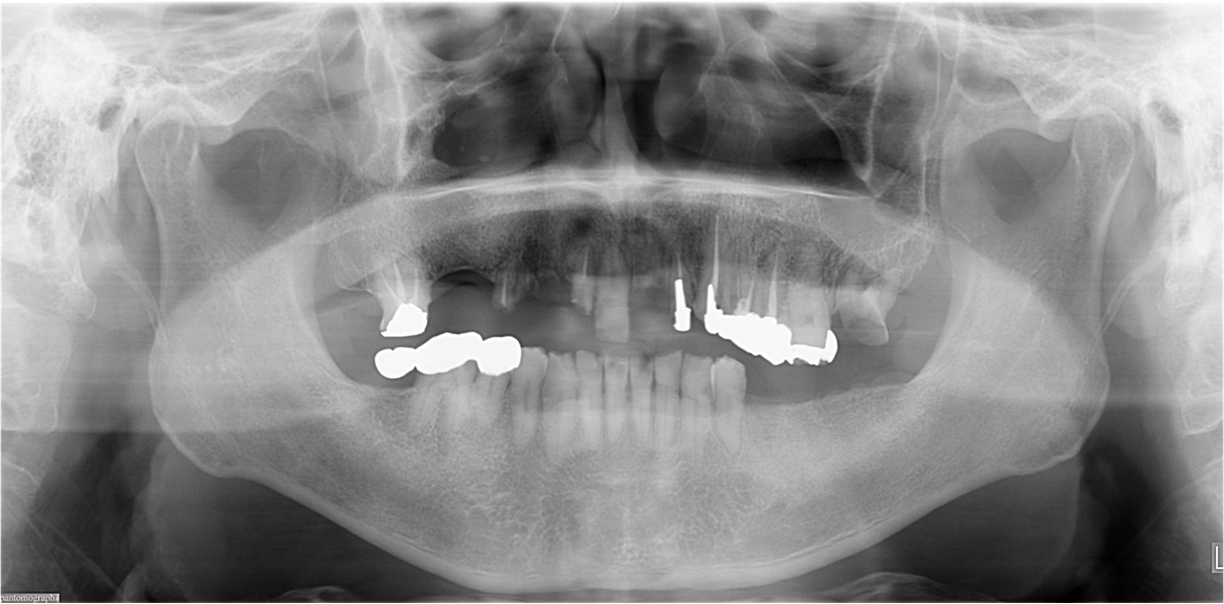

多数歯欠損のインプラント治療の症例(うえだ歯科)

症例詳細

| 主訴 | 歯がグラグラで噛むことができない。インプラントをして欲しい。 |

| 治療内容 | 歯周病で骨の吸収が重度で保存不能なため抜歯、仮の入れ歯を作り、6ヶ月の抜歯窩の治療の後に、インプラントのCTによる診査診断を行い、下顎に6本インプラント埋入と同時に仮歯を入れる。その後、上顎は8本のインプラント埋入と同時に仮歯を入れる。左右上6はソケットリフトによる上顎洞拳上術を行う。その後免荷期間6ヶ月待ってセラミックを用いた上部構造作製、装着しメンテナンスに移行する。 |

| 治療費 | 9,000,000円(税込) |

| 治療期間 | 2年3ヶ月 |

| 治療回数 | 90回 |

| 想定されたリスク | 重度の歯周病により無歯顎になったため、プラークコントロール不良による、術後のインプラント周囲炎が懸念される。歯冠の部分はセラミックなため欠ける可能性がある。 |